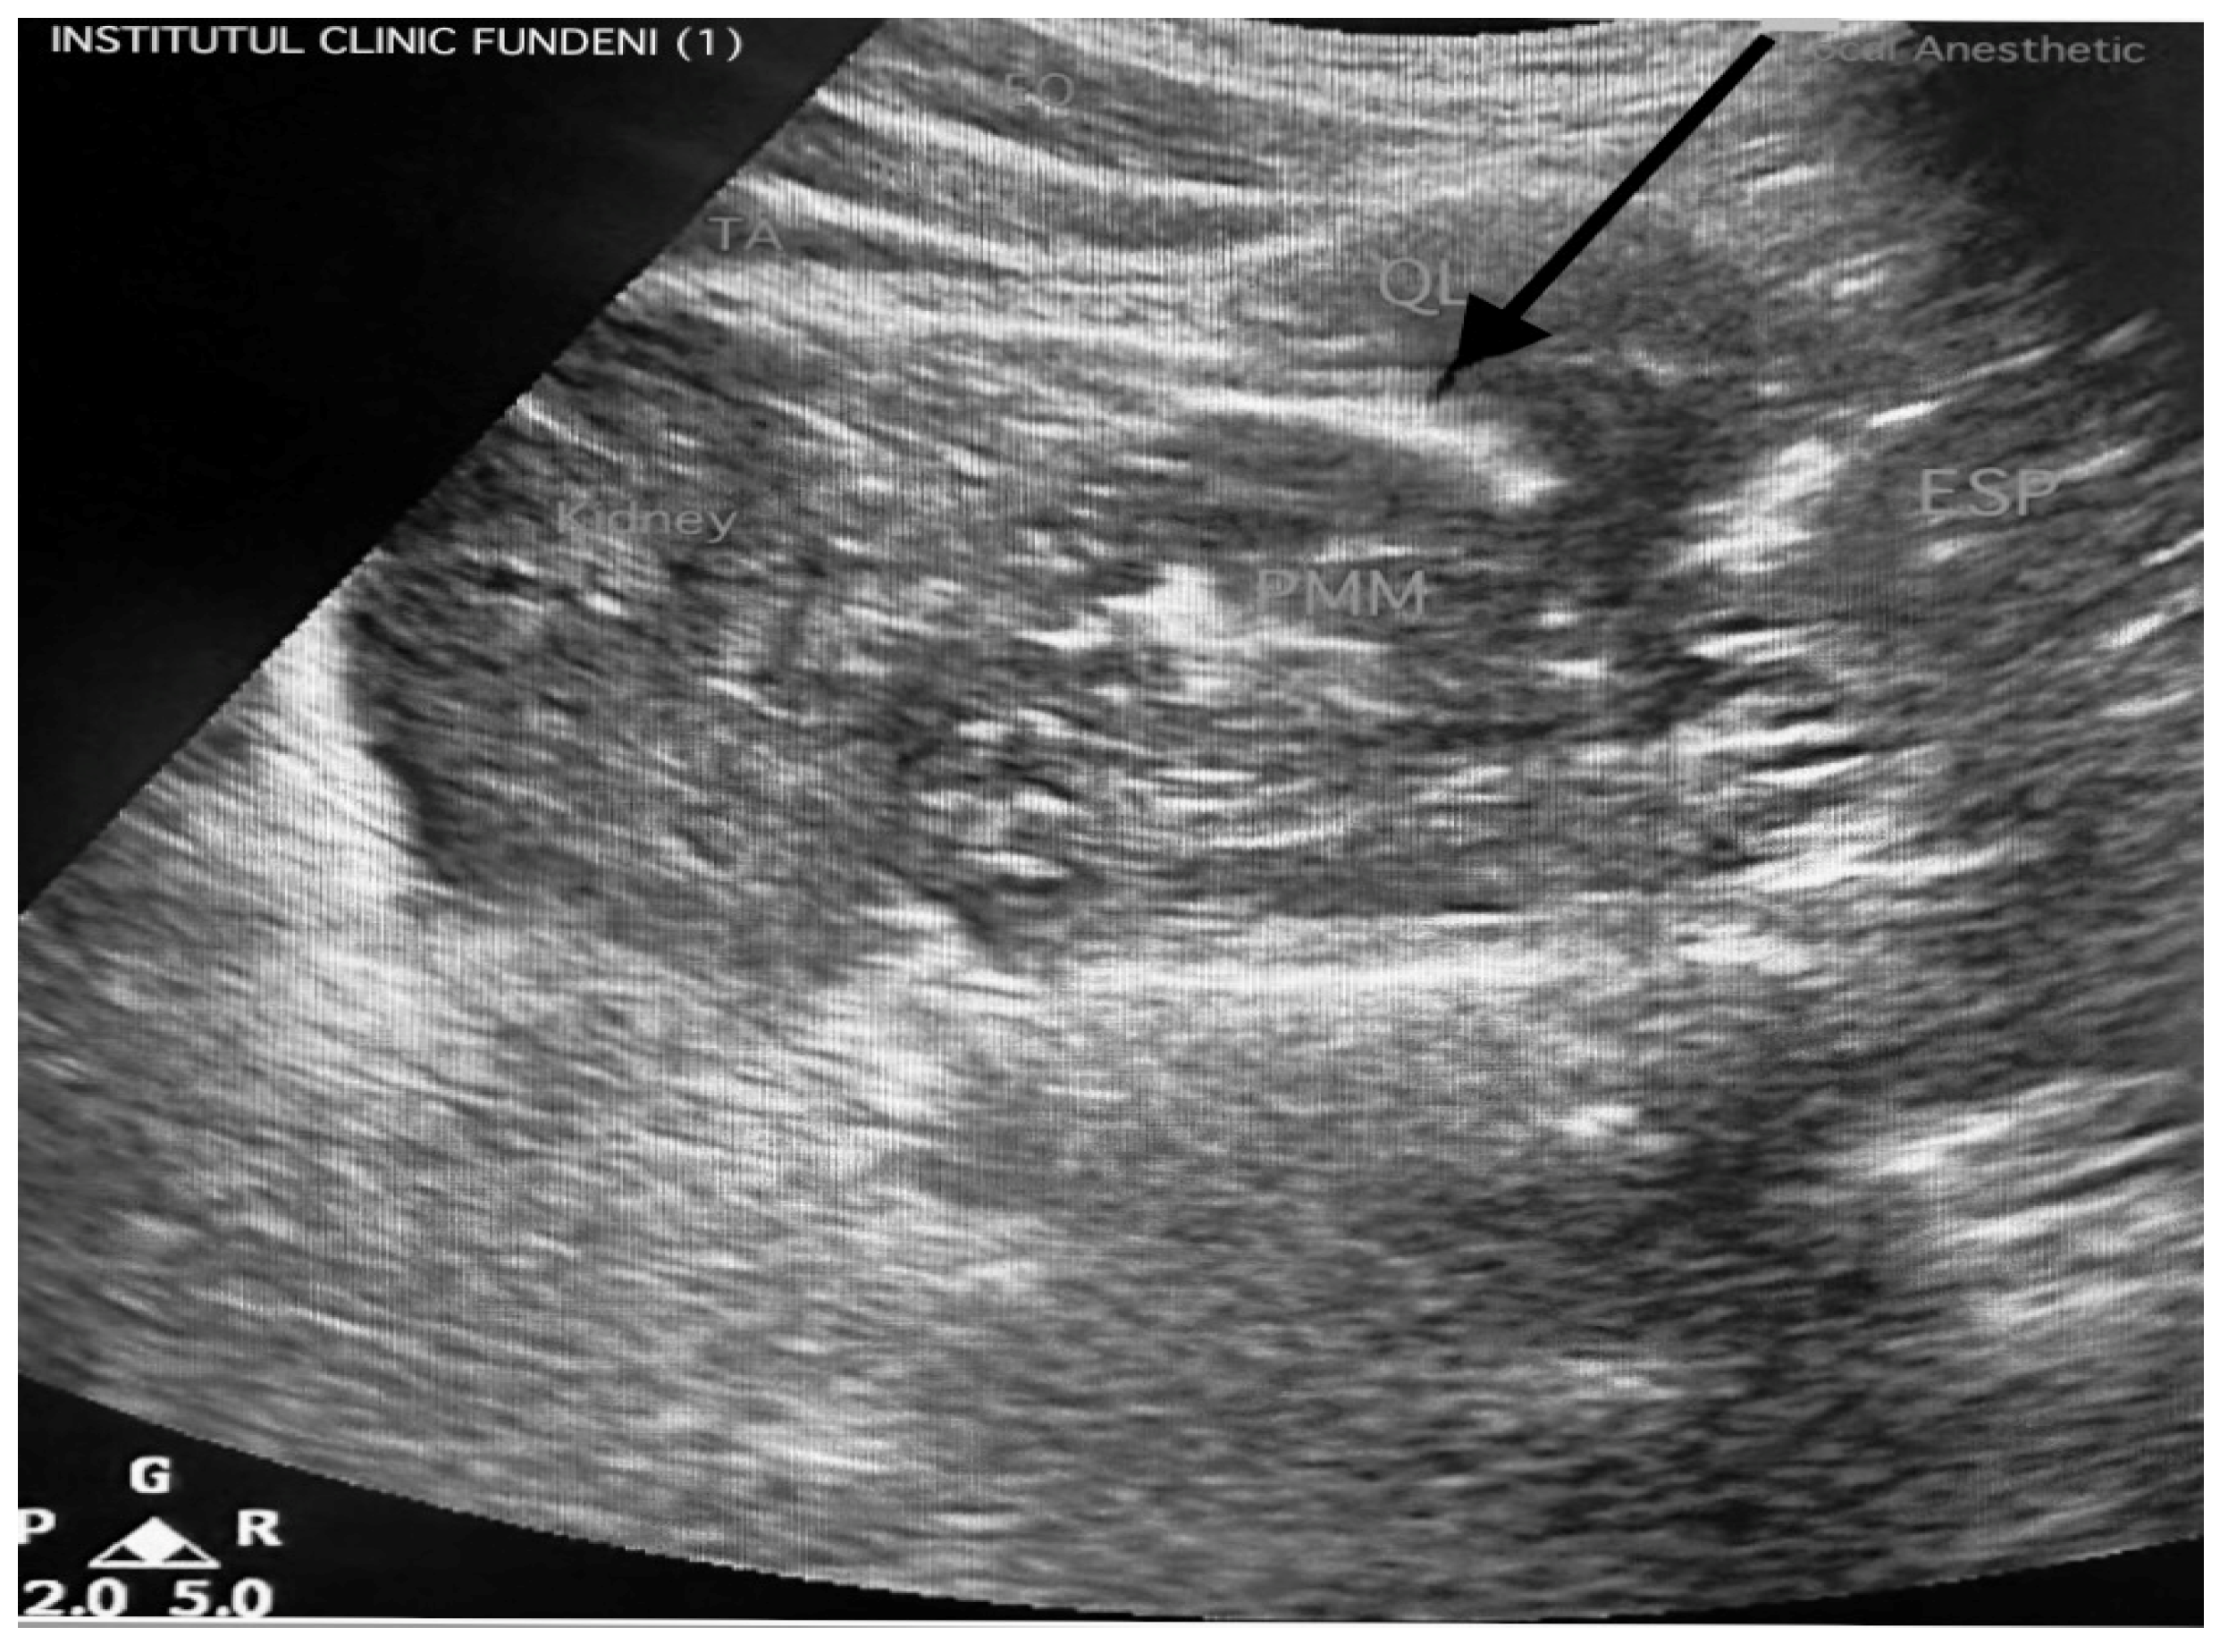

2.4.1. Group QL Block (n = 62)